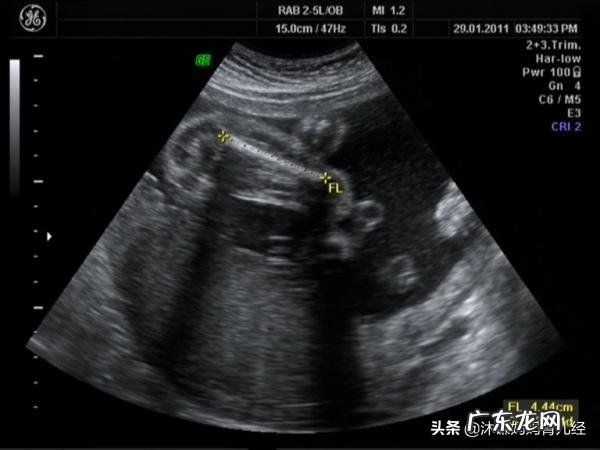

按照每周7天来计算,怀孕四十天大概是孕6周左右,此时胎宝宝头部、额面器官、神经等器官逐渐分化,通过B超,可以清晰得看到胎囊,并可见胎心胎芽(有时胎心也有可能会出现的晚一些) 。

所谓孕囊,就是怀孕最初的形态,是原始的胎盘组织,被羊膜、血管网包裹的小胚胎 。在怀孕40天的时候,孕囊大概能达到1cm左右 。

一般在怀孕四十天左右,准妈妈需要去医院做一次检查,看有没有胎心胎芽及其他发育情况 。而测量孕囊的大小主要有两个作用,即估算孕周,及根据末次月经的时间对于孕囊大小来推断宝宝发育过程中是否存在缺陷 。

在回答这个问题前,我们先来了解一下宝宝孕早期的三部曲,孕囊,胚芽,心搏 。其中孕囊是第一步,也就是讲孕囊出现在宫腔内提示宫内孕,但是孕囊也就只有这个功效,临床上不会因为孕囊大小来评估停经时间,但是当孕囊最大直径大于2.5cm时,仍没有出现胚芽心搏,那么提示胎停 。

文章插图

正常情况下,腹部B超一般在孕6周出现孕囊,而阴超下一般孕5周就可以出现孕囊了,孕囊只是一个小水泡,只有小水泡中长出胚芽,心搏,才提示生命的出现,而且近20%左右的胚胎存在胎停可能,所以单看孕囊大小是没有用的,最多能提供的信息就是宫内孕,可以排除宫外孕 。

从B超的专业来讲,这个孕囊容易所探头的压力导致孕囊形态改变,也会影响大小,所以根据孕囊判断胎儿性别及根据孕囊大小判断胎龄都是不靠谱的 。

总结,孕囊只是提供宫内孕的证据,不能由此推算孕周及胎儿是否安好 。祝好孕 。

女性朋友在停经35天左右,确认怀孕后通过B超就可以在宫腔内看到孕囊,从孕囊里面可以看到明显的卵黄囊、胚芽、胎心搏动 。孕40天也就是6周左右,此时的孕囊直径约2㎝;孕10周时约5㎝,孕囊位置在子宫的宫底、前壁、后壁都属于正常,孕囊的形态是圆形、椭圆形且清晰 。

如果孕囊为不规则、模糊且位置在下部,孕妈同时又伴有腹痛、出血时,则说明孕囊发育异常,有流产迹象,需要孕妈及时处理 。